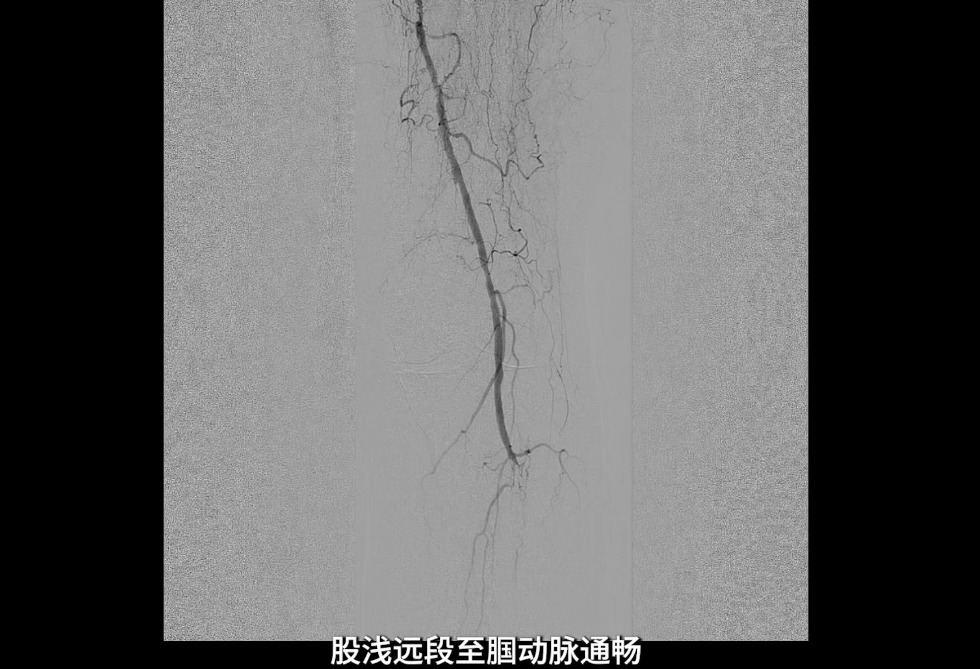

左侧股浅动脉中上段明确长段狭窄并闭塞,病变长度约15cm,股浅动脉远段至腘动脉管腔通畅。

膝下动脉三支主干均闭塞,胫后动脉远端经侧支循环显影;腓动脉远端为“休眠血管”,通过与胫后动脉的交通支实现逆向显影。